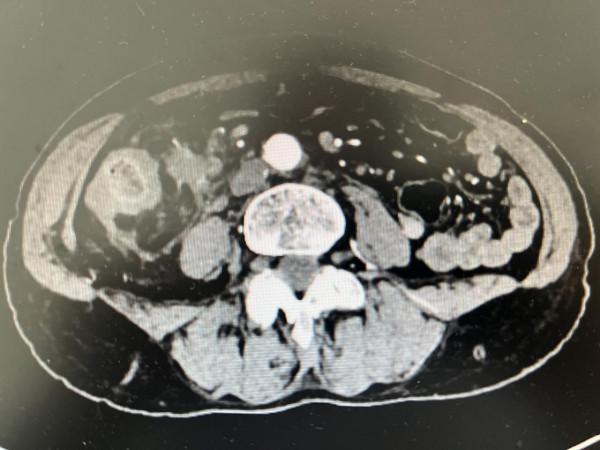

影像學檢查提示:1.升結腸及迴腸末端腸壁增厚,考慮惡性腫瘤;2.腹腔、腹膜後多發腫大淋巴結考慮轉移;3.腹腔內脂肪間隙模糊,腹膜增厚,考慮轉移的可能。

2021年9月20日,複查CT提示:1.結腸佔位,較前縮小;2.腹腔、腹膜後多發腫大淋巴結,後腹膜區腫大淋巴結較前縮小。

複查CT提示:1.結腸佔位,化療後改變;2.腹腔多發腫大淋巴結。